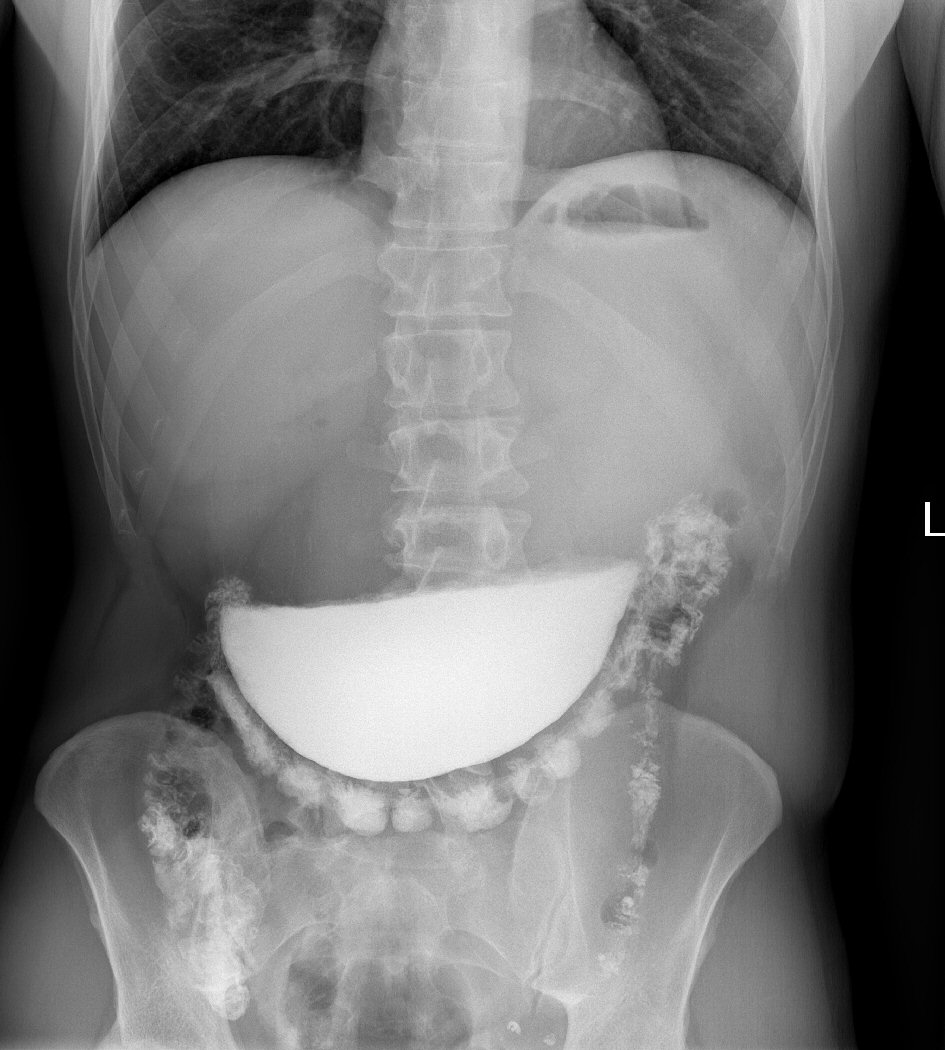

A 38-year-old patient arrived at the surgical department complaining of long-term problems with food intake. Patient history showed previous surgery for congenital pylorostenosis in childhood. The patient was examined at the surgeon’s office and the surgeon ordered a native X-ray and ultrasound examination; both exams showed no pathology. A computed tomography (CT) scan was performed (Fig. 1) which raised the suspicion of gastrostasis. With the suspicion of recurrent pylorostenosis a radiologist was consulted and a contrast-enhanced examination of the upper gastrointestinal tract was indicated. Radiologist elected to use barium sulphate as the contrast agent. The examination demonstrated stenosis of the pylorus with gastrostasis which was confirmed in a repeated X-ray after 30 min with stasis of all the contrast agent in the stomach (Figs. 2, 3). The surgeon suspected a benign stenosis of the pylorus and scheduled the patient for planned surgical intervention. In 5 days the patient made a unplanned return to the surgeon’s office complaining of substantial and increasing pain in left epigastrium. The left epigastric region was tender and considerable pain was felt on palpation. The surgeon ordered an X-ray examination that displayed evidence of the stasis of a large amount of contrast agent in the stomach (Fig. 4). Inflammation parameters were not elevated (C-reactive protein (CRP) 0.3 mg/L, procalcitonine 0.086 µg/L). The patient was admitted to the surgery ward. Nasogastric tube was inserted with an unsuccessful attempt to evacuate the contrast agent. During hospitalization the patient’s condition deteriorated and an immediate laparotomy was indicated to find a surgical solution to the patient’s condition. During surgical intervention a tumorous lesion was identified on the pylorus with the diameter of 5 cm, dilated stomach and adhesions. After mobilizing the stomach and duodenum a large amount of precipitated and sedimented barium sulphate was carefully scooped out with emphasis on preventing its intraperitoneal spillage. A BII partial stomach resection was performed, the removed tissue was send to pathology department for histological examination. Roux-en-Y gastrojejunal anastomosis was established, a repeated lavage of the peritoneal cavity was carried out. Tygon tube 27 drainage was inserted near the stump of the duodenum and into the rectovesical excavation. After surgical intervention the patient was moved to the central intensive care unit. Intense antibiotics therapy was initiated, patient received infusions and nutritional support. On the second day following surgery patient’s condition worsened with the elevation of inflammation markers (CRP 78.9 mg/L, procalcitonine 4.45 µg/L). Leak of the anastomosis or contrast agent spillage with peritonitis was suspected. A CT scan was indicated, however identified no contrast agent spillage intraperitoneally and no anastomosis failure. Subsequently an ampule of methylene blue in 100 mL of physiological solution was administered through the nasogastric tube, the drained exudate was observed for signs of methylene blue, but none was found. The drainage bags contained 200 mL of sanguinolent fluid with no hint of methylene blue. In the morning of the third day following surgery another CT exam was indicated (Figs. 5, 6), and a small amount of contrast agent was identified in the paragastric intraperitoneal region. The previous CT exam was reviewed and the same amount of contrast agent was identified next to the stomach, active leak was therefore not suspected. Laboratory results were however worsening with increase in inflammation parameters (CRP 267.60 mg/L, procalcitonine 25.90 µg/L). Sepsis was suspected, but the patient remained afebrile. Due to anastomosis dehiscence being repeatedly unconfirmed on CT exams, considered surgical revision was not performed. Antibiotic therapy was revised and vasopressor support was introduced. On the fourth day following surgery patient’s condition improved, therapy with antibiotics and vasopressors continued, and the amount of exudate drained was significantly lower. The surgical wound was found to be dehiscent and phlegmonous, local therapy was applied. A week after the surgery patient’s condition was improving further with stools being passed. Vasopressors were discontinued. Inflammation parameters improved considerably (CRP 78.60 mg/L, procalcitonine 2.85 µg/L). Two weeks after the surgery with further improvement of inflammation parameters (CRP 13.80 mg/L) the patient was discharged. Histological exam of the resected tissue has confirmed the diagnosis of malignant stenosis of the pylorus (moderately differentiated adenocarcinoma) and the resection margin was positive for carcinoma. A repeated resection with the revision of the anastomosis was indicated. The surgical wound again healed per secundam. The patient was referred to the department of clinical oncology where chemotherapy was initiated. The last positron emission tomography (PET)/CT exam from July 9, 2018 found no metastatic lesions.

![]() Click for large image | Figure 4. X-ray examination demonstrates stasis of the contrast agent, minimal amount of contrast agent passed through the pylorus. |